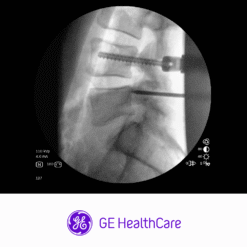

Vista clara de anatomía

Detalle de imagen 1: 1 del detector CMOS a la pantalla 4K con cadena de imagen Clear View.

con CFD y Live Zoom, y revise la última secuencia de flúor con Fluorostore.

Visualice fácilmente imágenes detalladas de gran tamaño en un monitor 4K ajustable a la línea de visión del cirujano.